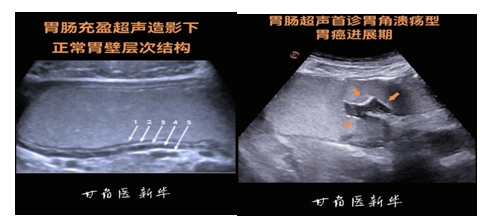

胃肠充盈超声造影技术是通过造影剂充盈胃肠腔,清除胃肠腔内气体、内容物等对超声波的干扰,使声波能顺利穿透,从而清晰显示胃肠壁结构及其病变的方法。这项技术既无痛又无创,弥补了传统方法(如胃镜)带来的痛苦和心理障碍,患者无需插管、麻醉,只需喝完一杯类似米糊的 “糊糊”(胃肠充盈超声造影剂),就能完成检查。